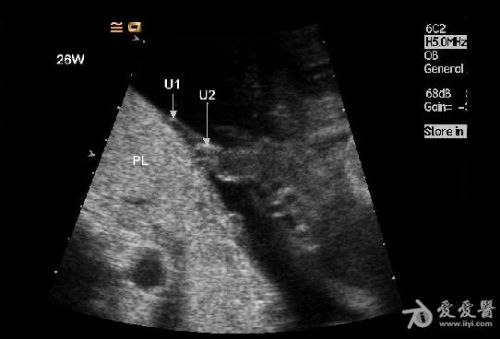

是双胎,其中畸形的那个明显没有上半身及头部,只有下半身和一点点短小的左上肢。

1、双胎中一胎形态、结构发育正常,另一胎出现严重畸形,以上部身体严重畸形为主,可有下部身体如双下肢等结构。

3、上部身体严重畸形,可表现为无头、无双上肢、胸腔发育极差。

5、无心畸胎常有广泛的皮下水肿声像改变,在上部身体常有明显的水囊瘤。